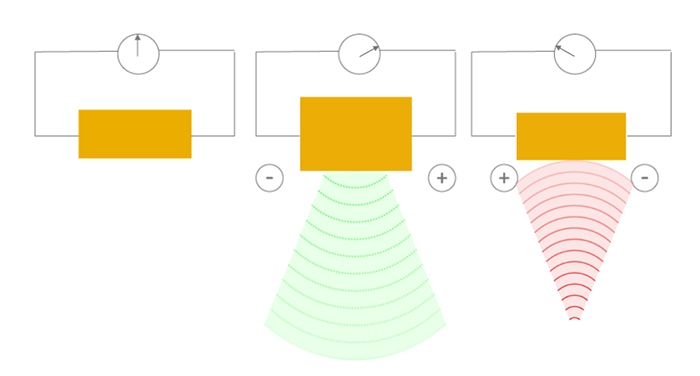

The reverse effect is defined as the generation of a mechanical wave resulting from the application of an electric field. When an electric field is applied, the charge carriers are shifted in the piezoelectric materials, leading to a macroscopic change in the length of the material (inverse piezoelectric effect), thus to the emission of the ultrasound wave. The resulting sound waves propagate in the surrounding medium, where their speed varies according to the density and the elastic properties of the medium.

The direct effect is the generation of an electrical signal following the application of a mechanical force. The piezoelectric effect converts the mechanical energy (received ultrasound wave), into electrical energy, due to the crystal deformation. This is how ultrasound transducers receive the sound waves.

It is known that the crystals in the ultrasonic probe change shape, and emit ultrasonic waves when stimulated by an electrical current. These sound waves reflect off the surface of the body and collide with quartz crystals, which then produce an electrical current.